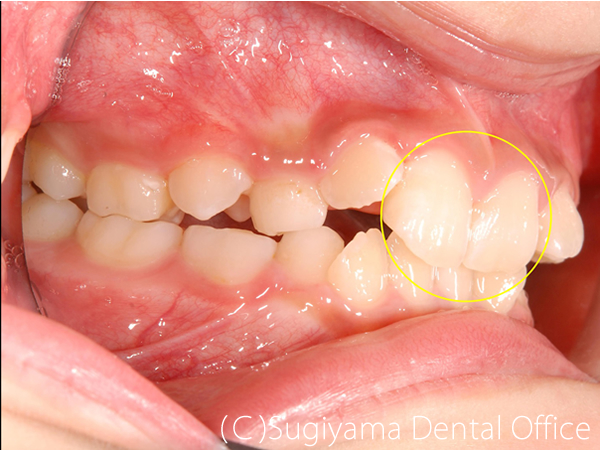

10歳の女性です。 術前写真を見ると、上の前歯2本が内側に傾斜していることがわかります(丸印)。 このような歯の傾斜によって下のあごの位置が奥に押し込まれ顎関節症になる方が少なくありません。

術後1年後には綺麗な歯並びになっただけでなく、機能的なあごの運動ができるようになりました。